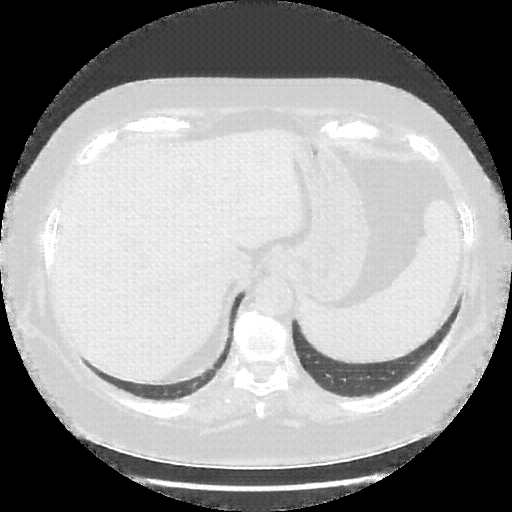

Generated VENOUS CT scan (A→B translation)

Full window (WL 1023.5, WW 4095 β†’ Low βˆ’1024, High +3071)